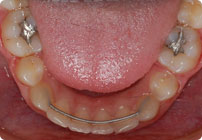

Caso: 11 años

Adolescente: Clase II

Mordida Cruzada Posterior

Sin extracción

Sin uso de expansores

6 alambres superiores

5 alambres inferiores

Sin uso de elásticos

Retenedores: Interior Fijo de TMA y Hawley en superior

Tiempo de tratamiento: 14 Visitas